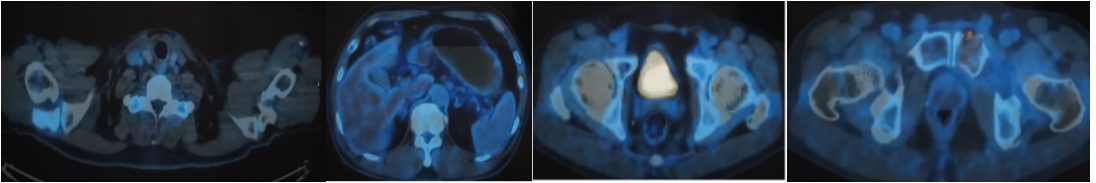

第3-8周期使用塞利尼索(40mg,QW)联合替雷利珠单抗(200mg)和奥布替尼(100mg,QD)方案治疗。治疗期间复查颅脑PET/MRI和全身PET/CT评估疗效:持续CR。

上图、中图:颅脑PET/MRI图

下图:全身PET/CT图